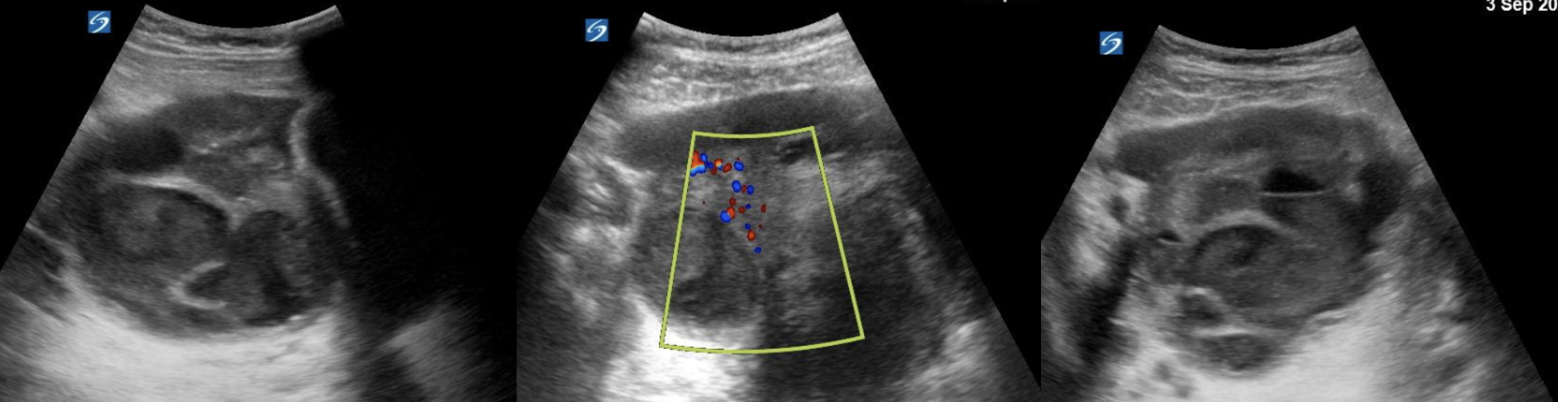

Tubo-ovarian Abscess (TOA)

PoCUS features

- Ill-defined borders, often multi-loculated

- Thick, irregular walls

- Heterogeneous internal echoes from debris, pus, or clot

- Internal septations may be present, showing the “waist sign”

- The pathognomonic finding may be the “cogwheel sign”, referring to the cross-sectional appearance of infolding projections into the fallopian tube, giving the appearance of a cogwheel (Radiopaedia, 2022).

- Absence of discrete solid vascular nodules helps distinguish from neoplasm

- Frequently associated with pelvic free fluid, which may be simple (anechoic) or complex (echogenic)

- Increased vascular flow in the wall/septa on Doppler due to inflammation (hyperemia)